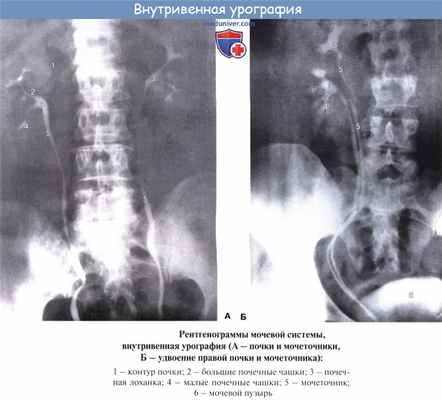

- Внутривенная или ретроградная урография. В вену (или в мочеточник через уретру) вводится специальный рентгенпозитивный препарат и в то время, когда он выводится почками, выполняются снимки, позволяющие увидеть протяженность стриктуры мочеточника, ее размер, оценить снижение выделительной способности почек.

Рентгеноанатомия мочеточников. На рентгенограмме мочеточник имеет вид узкой тени с четкими и гладкими контурами (рис. 7). По выходе из почечной лоханки правый и левый мочеточники приближаются к поперечным отросткам поясничных позвонков, образуя в поясничной части изгиб в медиальную сторону. В полости таза мочеточники изогнуты в латеральную сторону. Перед впадением в мочевой пузырь они вновь изогнуты медиально. При рентгеноскопии мочеточников у живого человека, помимо описанных анатомических сужений, можно видеть физиологические сужения, связанные с перистальтикой мочеточников.

Рентгенконтрастная урография (экскреторная, инфузионная, ретроградная) дает возможность визуализировать ткани почек и мочевыводящие пути, определить сужение мочеточников, протяженность стриктур, оценить снижение выделительной способности почек.

Мочеточник на рентгенограмме имеет вид длинной и узкой тени, идущей от почки до мочевого пузыря. Контуры его четкие и гладкие. Мочеточник образует искривления в двух плоскостях — сагиттальной и фронтальной. Практическое значение имеют искривления во фронтальной плоскости : в поясничной части в медиальную сторону, а в тазовой — в латеральную. Иногда мочеточник в поясничной части выпрямлен. Искривление тазовой части постоянно.

По ходу мочеточника отмечается, кроме описанных выше анатомических сужений, ряд физиологических сужений, появляющихся и исчезающих во время перистальтики.